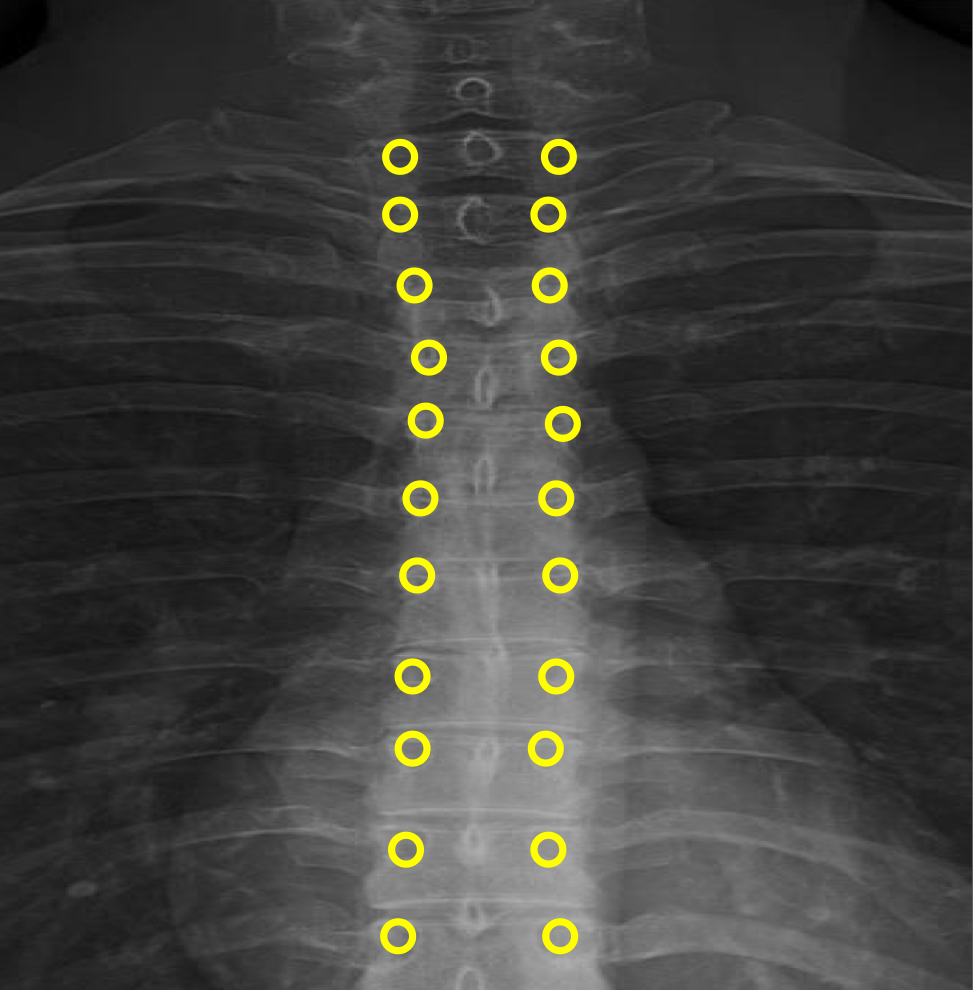

What view is this?

AP (Anterior to Posterior) Thoracic

What is this?

Junction of Laminae

What is this?

Pedicle Shadows

What is this?

Vertebral Waist

What is this?

Inferior Endplate Tips

What is this?

Superior Endplate Tips

What is this?

Disc Spaces